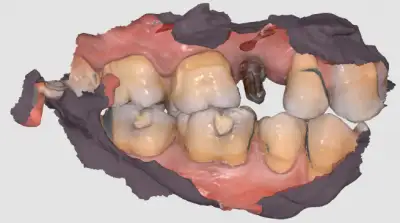

Digital scan image

- Intra oral scanning done using digital scanner for PMMA crown